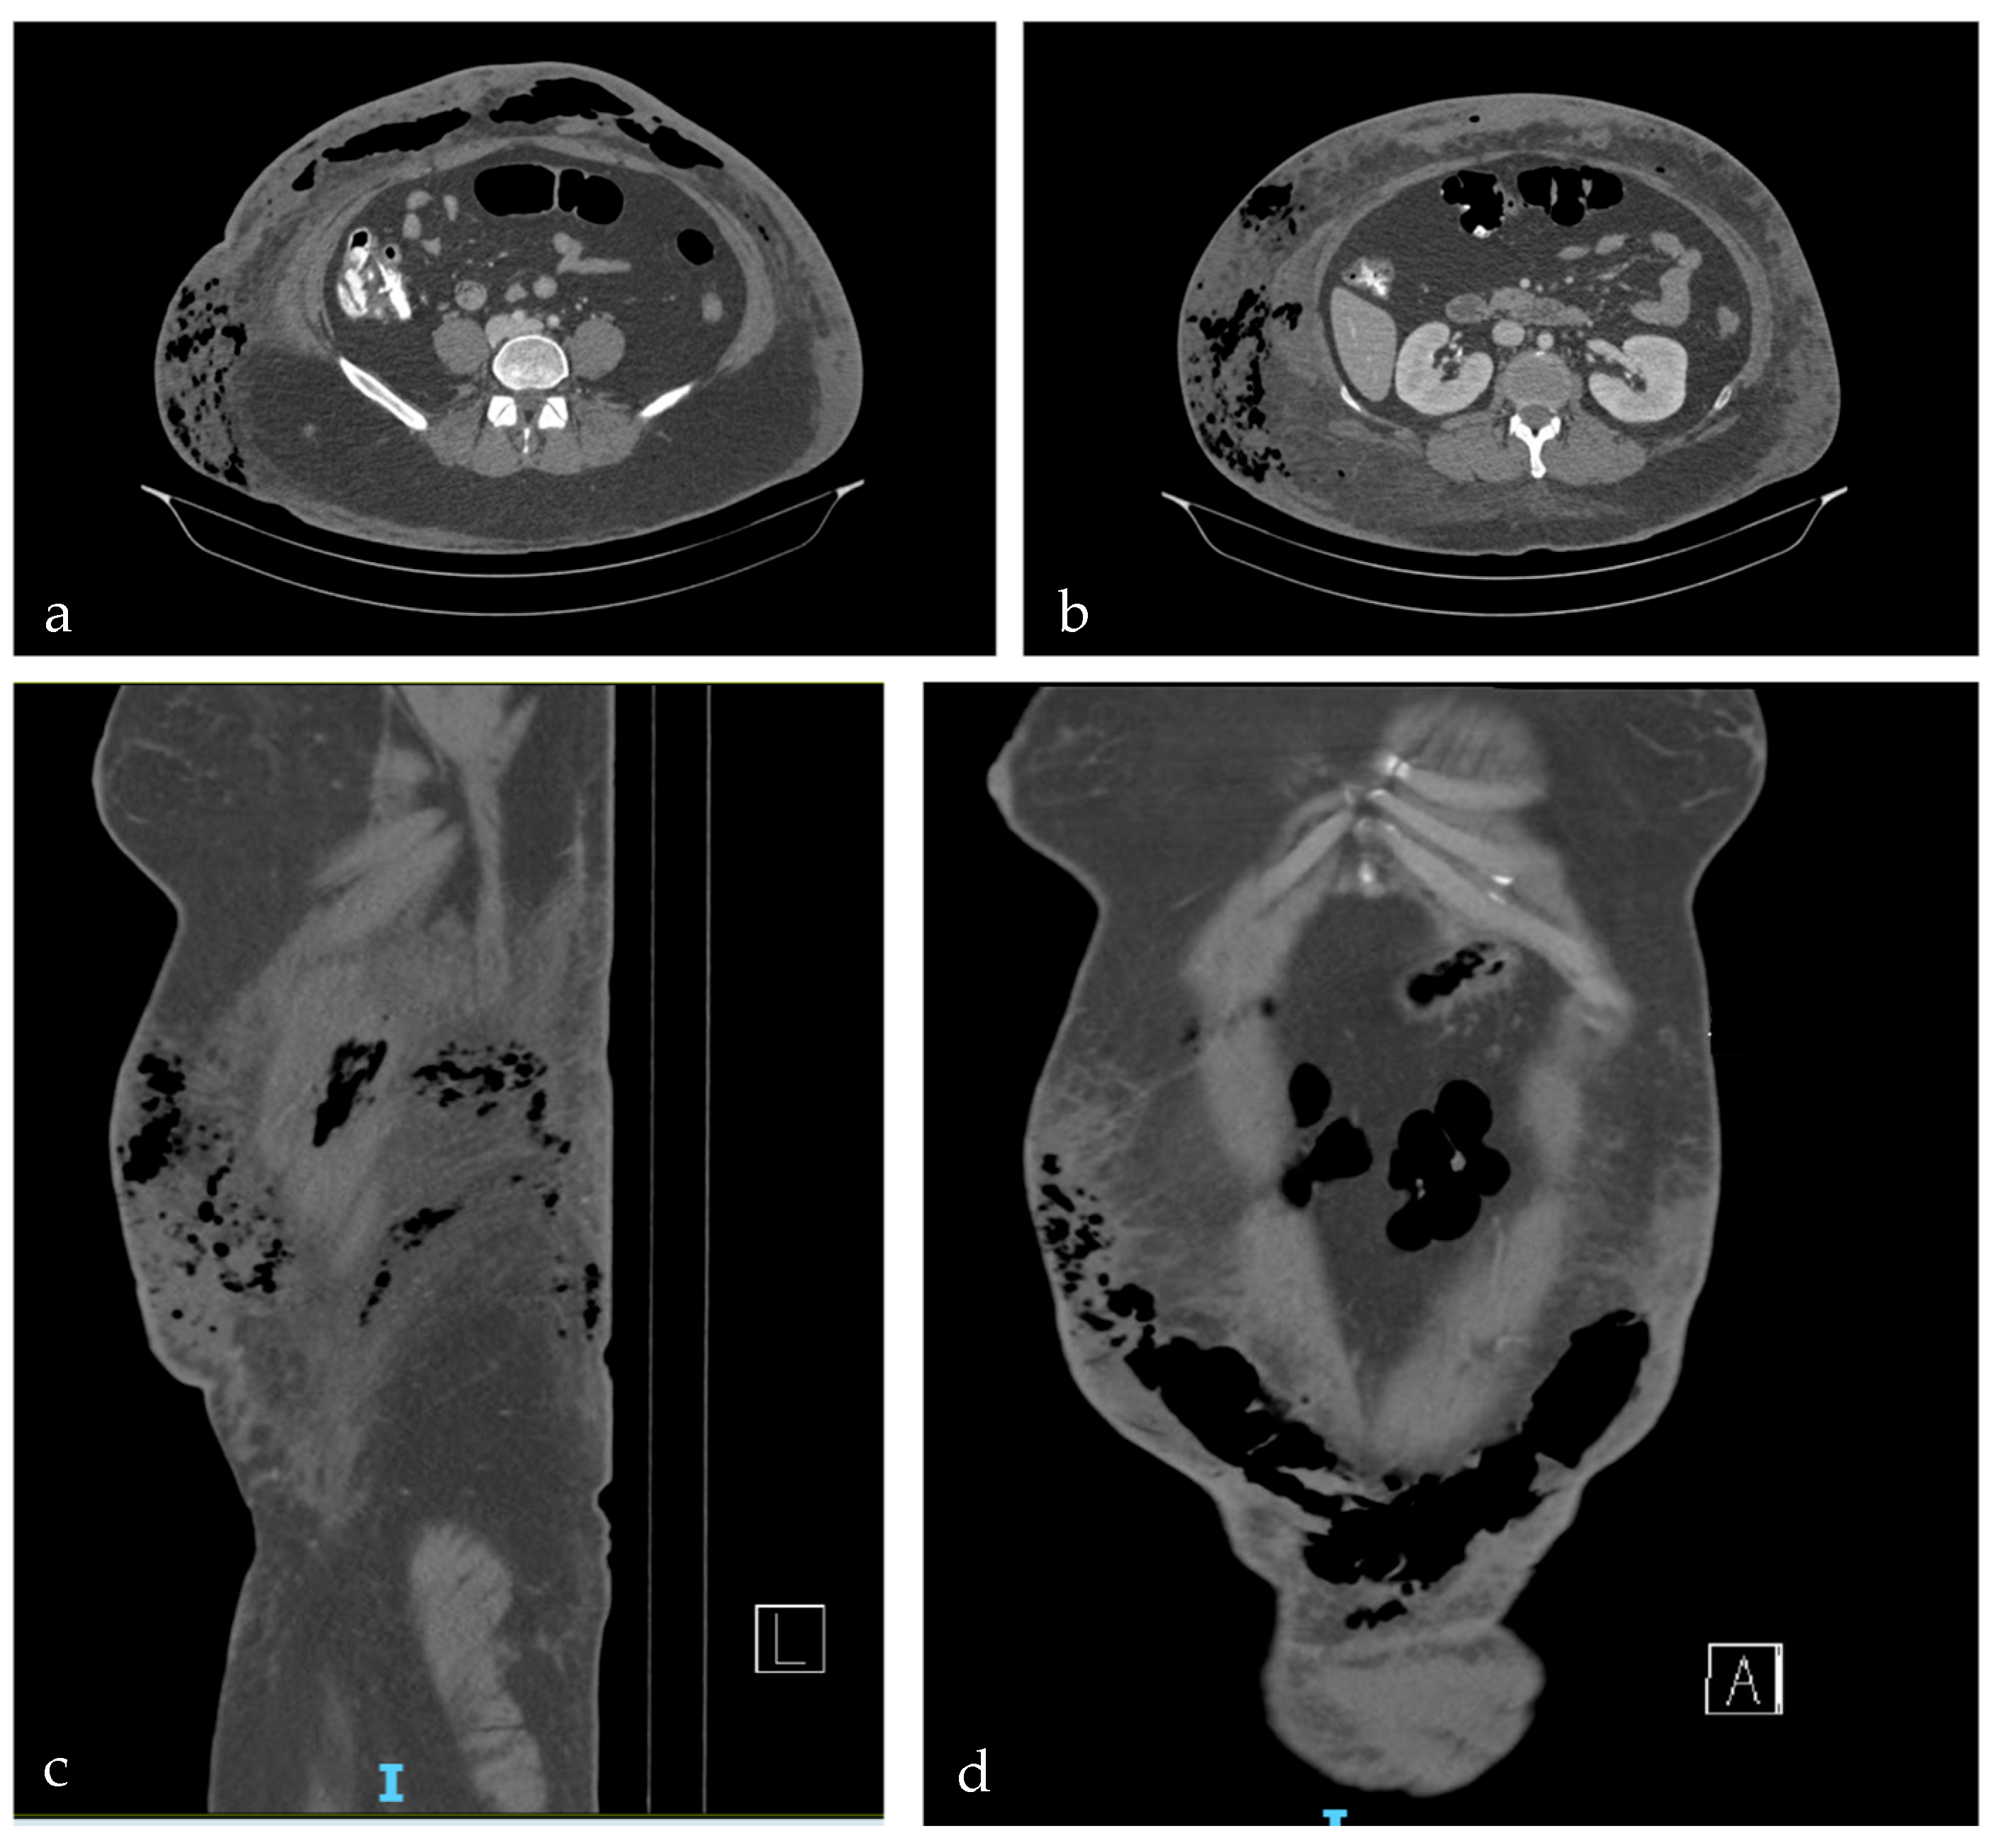

2. Case Report